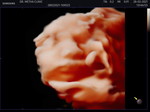

āļāļģāļŦāļāļ23āļāļ. āļāļāļāļāļĩāđ37+4 āđāļŦāļĄāļ·āļāļāļāļ°āļĄāļĩāđāļāđāļāļēāļāļēāļĢāđāļāđāļāđāļāļ·āļāļ āđāļāļĢāļēāļ°āđāļĄāļ·āđāļāļ§āļąāļāļāđāļāļāđāļāļĢāļ.āļŦāļĄāļāļāļāļāļĄāļāļĨāļđāļāļāļĩāļāļāļąāļ§āļāđāļē10āļāļēāļāļĩāļāđāļāļāļĢāļąāđāļ āļāļĒāļēāļāđāļāļāđāļĨāđāļ§āļāļ° āļāļ§āļāđāļāļāļąāđāļāļāļąāļ§

āļāļģāļŦāļāļ 5āļāļ64 āļāļĩāđāļāđāļ° āļāļāļāļāļĩāđ34wāđāļĨāđāļ§ āđāļŦāļāļ·āđāļāļĒāļāđāļēāļĒ āļāļ§āļāđāļāļīāļāļāļĢāļēāļ āļāđāļāļāđāļāđāļāļāđāļĄāļē āļāļĩāđāļāđāļāļĒāļĄāļēāļ āļāļĢāļ°āļāļąāļāļāļĢāļ°āļāļāļāļŠāļļāļāđāđāļĨāđāļ§āļāđāļ° āļĨāļđāļāļāđāļģāļŦāļāļąāļāđāļāļīāļāđāļ2600āđāļĨāđāļ§

āļāđāļāļāđāļĢāļāļāđāļ° āļāđāļāļāđāļāđāļāļāļđāđāļŦāļāļīāļāļāđāļ° āđāļāļāļāļąāđāļāļāļ·āđāļāđāļ§āđāđāļĨāđāļ§āļāļāļāļāļĩāđ GA 29+5 wk āđāļĨāđāļ§ āļāđāļāļāļāļīāđāļāđāļāđāļāļāđāļ° Due 25 āļāļ āļāđāļ° āđāļĄāđāđāļāļāļāđāļģāļŦāļāļąāļāļāļķāđāļāđāļŦāļāļĄāļē 15 kg āđāļĨāđāļ§āļāđāļ°

āļ§āļąāļāļāļĩāđāļāļĢāļ 30 wk āļāđāļ° āļāļāļāļāļĩāđāļāđāļāļ 1351 gm āļāđāļ°

āļāļģāļŦāļāļ 26 āļāļāļāļāļĩāđ 37+1 āđāļĄāļ·āđāļāđāļāđāļēāļĄāļĩāļĄāļđāļāđāļĨāļ·āļāļāļāļīāļāļāļķāļāļāđāļ° āđāļĄāđāđ āļāđāļēāļāļāļ·āđāļāđāļāļāđāļŦāđāļāļĢāļ§āļāđāļāļ§āļīāļāļāđāļēāļāđāļŦāļĄāļāļ° āđāļĢāļēāļāļēāļ āļĢāļ.āđāļāļāļāļ āđāļāļēāđāļŦāđāļāļĢāļ§āļāļāđāļāļāļāđāļ°

3 āļ.āļ. āđāļāđāļāļāļāļāļĩāđāļāļ·āļāļāļ§āļāļĢāđāļēāļ§āļāļīāļĄāļīāļĄāļēāļāļāđāļ° āđāļāđāļāļ°āļāļĨāļīāļāļāļąāļ§āļŦāļĢāļ·āļāļāđāļēāļ§āđāļāļīāļāļāđāļģāļāļēāļāļ°āđāļŦāļĨāđāļĨāļĒ 37+3āļ§āļĩāļ āļāđāļģāļŦāļāļąāļāļāđāļāļ3200 āđāļāđāļāđāļāļāļāļĩāđāļāļĩāļāļāļēāļāļĄāļąāđāļĒāļāļ°

āļĨāđāļēāļŠāļļāļāļāļāļāļāļĩāđāļāļāļ āļĢāļ.āļāļ° 30+2āļ§āļĩāļ āļĄāļĩāļāļēāļāļēāļĢāļāđāļāļāđāļāđāļ āđāļĄāđāļĄāļĩāļāđāļģāđāļāļīāļ āđāļĄāđāļĄāļĩāļĄāļđāļāđāļĨāļ·āļāļ āļŦāļĄāļāđāļŦāđāļĒāļēāļĢāļ°āļāļąāļāļāļēāļĢāļāļĩāļāļāļąāļ§āļĄāļāļĨāļđāļ āđāļĨāđāļ§āļāļĩāļāļĒāļēāļāļāļāđāļŦāđāđāļāđāļ

āļāļģāļŦāļāļāļāļĨāļāļ12 āļ.āļ. āđāļāđāļāđāļāļāļāļđāđāļāļēāļĒ āļŦāļĄāļāļāļąāļāļāļēāļ§āđāļāđāļĄāļ·āđāļāļ§āļąāļāļāļĩāđ 5 āļāļĩāđāļāđāļēāļāļĄāļē 30+2āļāđāļģāļŦāļāļąāļāļāđāļāļāļāļ°āļĒāļēāļāđāļāļāļĩāđ 1,700āļāļīāđāļĨāļāļĢāļąāļĄ āļāļĩāđāļĄāđāļāļķāļāļāļąāļāļĄāļēāļāļāļāļāļāļ